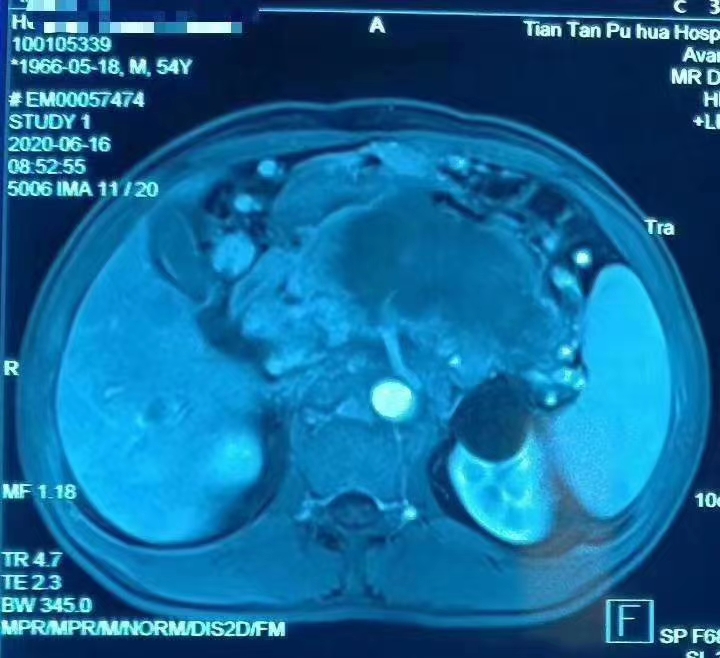

后两张图是7月份的肝转移瘤HIFU消融后,第一张14号术前检查,15号手术,第二张16号术后复查,总共相差2天。消融效果家属满意,医学同道称赞!